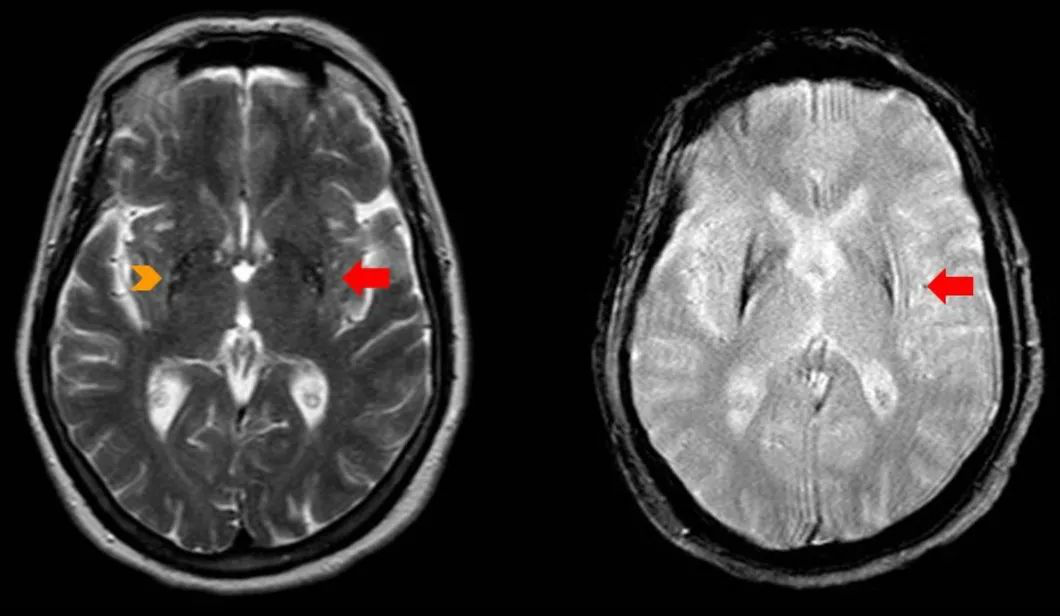

MSA-P 型的 MR 常出現(xiàn):殼核裂隙征、殼核后部 T2 低信號、殼核萎縮。

殼核裂隙征是指殼核外側(cè)邊緣 T2WI 高信號環(huán),MSA-P 型的殼核裂隙多集中在后 半部分,寬度大于 2 mm,存在著不連續(xù)性,存在著附近殼核的低信號,可存在殼核萎縮。MSA-C 型殼核裂隙集中在前半部或前 3/4,并且大部分是連續(xù)性的。

T2WI殼核后部線樣高信號,伴鐵沉積

殼核后部 T2 低信號是指在 T2WI 或 T2*殼核背外側(cè)低信號,病理證實是由于鐵蛋白丟失、鐵沉積引起。